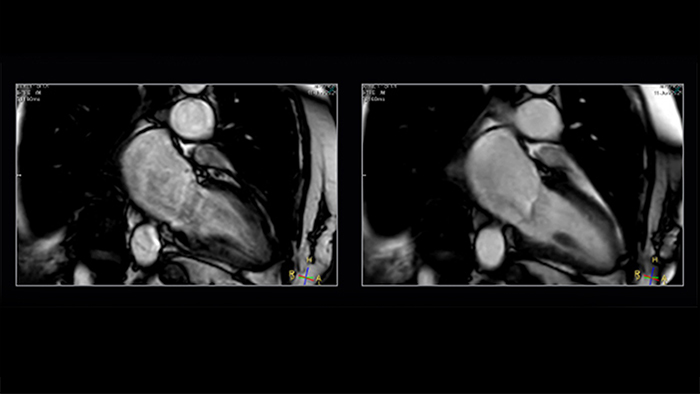

Shorter-breath holds are particularly impactful for patients who cannot manage the length of the breath-hold instruction. Mr. Strachan commented, “using Compressed SENSE sometimes pulls a non-diagnostic study into being a diagnostic study. That itself is very valuable.” For example, see Fig. 1

Figure 1. Shortening acquisition and denoising from C-SENSE provides confidence in long-axis cine of a patient with atrial fibrillation. Left to right: SENSE x2, C-SENSE x4